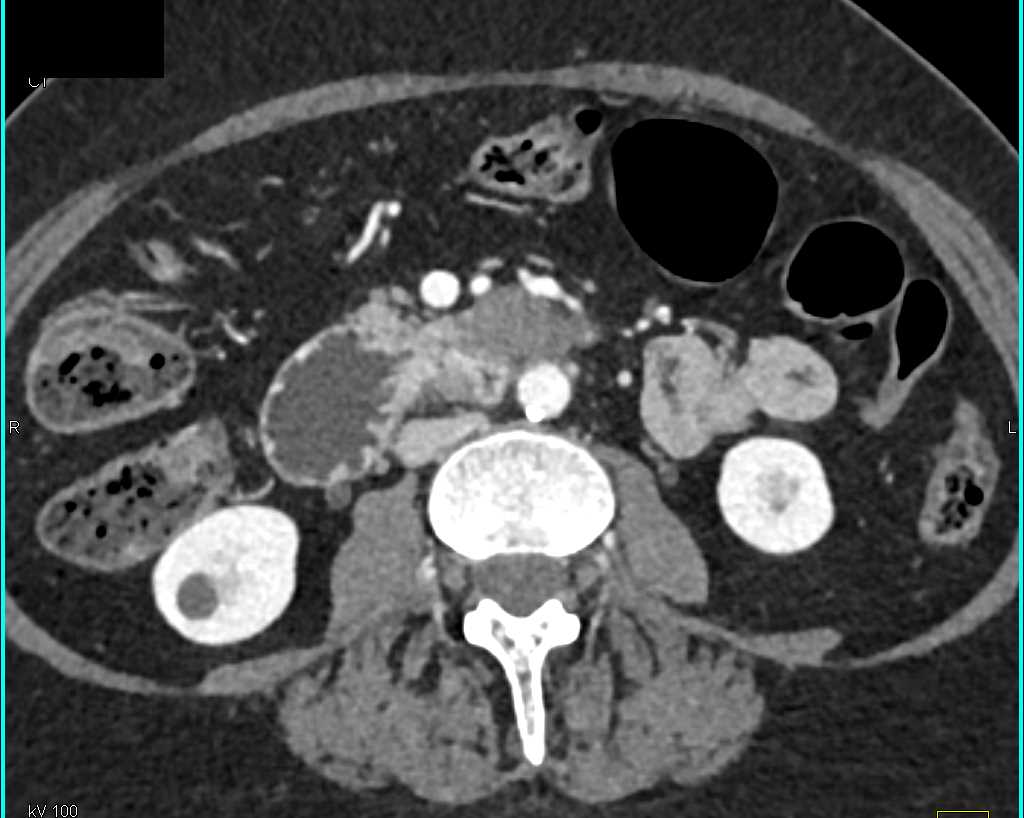

Duodenal Carcinoma with Obstruction